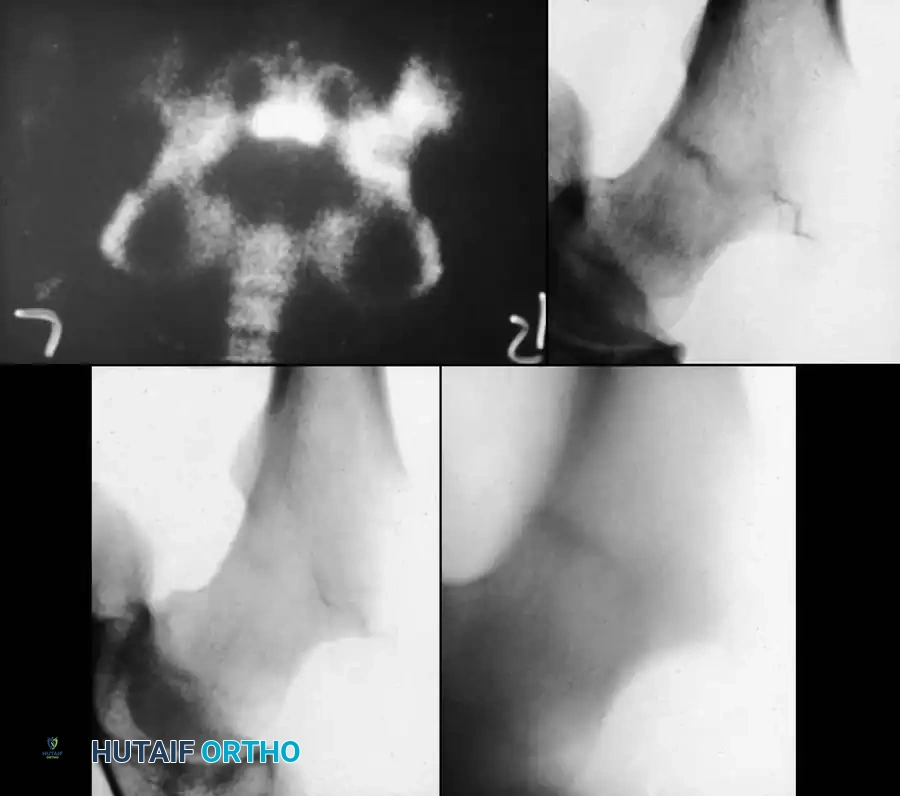

1. Osteonecrosis (Avascular Necrosis)

AVN is the most dreaded complication, occurring in up to 50% of displaced Type I and II fractures. It typically presents radiographically 6 to 12 months post-injury as sclerosis, fragmentation, and eventual collapse of the femoral head.

2. Coxa Vara

Coxa vara (neck-shaft angle < 120 degrees) results from loss of reduction, inadequate fixation, or premature closure of the medial aspect of the capital physis. It leads to a Trendelenburg gait and limb shortening.

3. Premature Physeal Closure

Injury to the physis from the initial trauma or iatrogenic damage from threaded hardware can cause complete or partial growth arrest. Complete arrest leads to limb-length discrepancy (the proximal femur contributes 15% of total leg length). Partial arrest leads to angular deformities (varus or valgus).